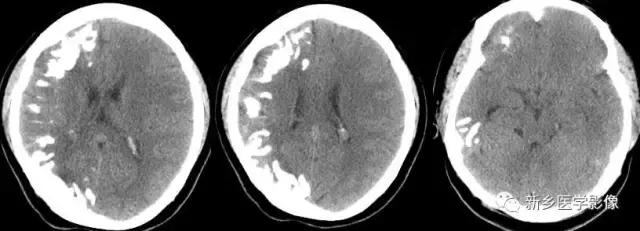

二、脑囊虫病

脑囊虫病慢性期,囊虫死亡以后,囊液逐渐被吸收,囊虫被机化,最后出现钙化。

钙化特点:多发、散在结节样钙化。钙化病灶通常较小、较圆、大小较均匀,少者单发或仅数个,多者可弥漫性分布于全部脑实质。